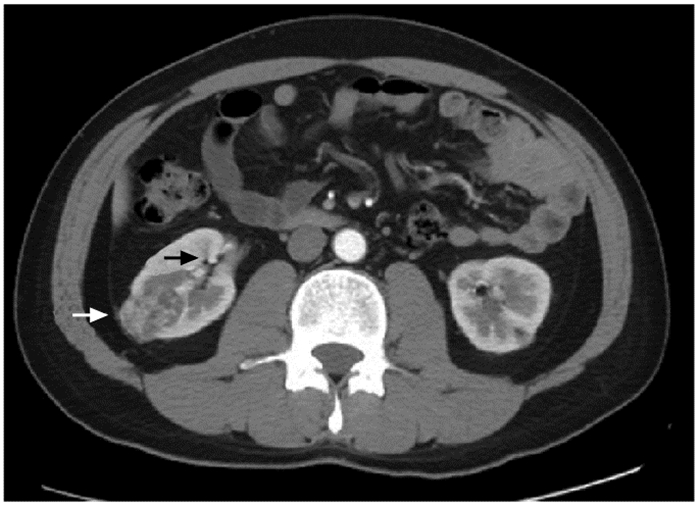

结果   14例AML患者中有1例相对孤立肾合并AML、7例多发AML、8例巨大AML(肿瘤最大直径>7 cm)、6例紧邻肾集合系统或肾门的AML以及2例合并出血破裂史AML, 病情复杂, 手术难度大。采取经腹腔镜或开放肾部分切除或肿瘤剜除术后, 顺利切除肿瘤, 病理检查提示肾AML, 术后定期门诊随访, 行CT扫描均无复发。全部患者术后肾功能保持良好, 术前和术后1个月血肌酐水平分别为(84.1±26.8)μg/ml和(97.5±37.0)μg/ml, 两组数据差异无统计学意义(t=-3.193, P>0.05)。

Results  Among 14 patients with renal AML, 1 had a relative solitary kidney with AML, 7 had multiple AML, 8 had huge AML (the maximum diameter of the tumor >7 cm), 6 had AML adjacent to the renal collection system or the renal portal, and 2 had AML combined with bleeding and rupture history; all cases were complicated and difficult to treat. All operations were successfully performed by laparoscopic or open partial nephrectomy or enucleation of the tumor, and pathological examination indicated renal AML. All patients were regularly followed up and no recurrence was found by CT scanning. The renal function of all patients was well preserved; the concentration of serum creatinine before and 1 month after the operation were (84.1±26.8)μg/ml and (97.5±37.0)μg/ml respectively, without statistically insignificant difference (t=-3.193, P>0.05).